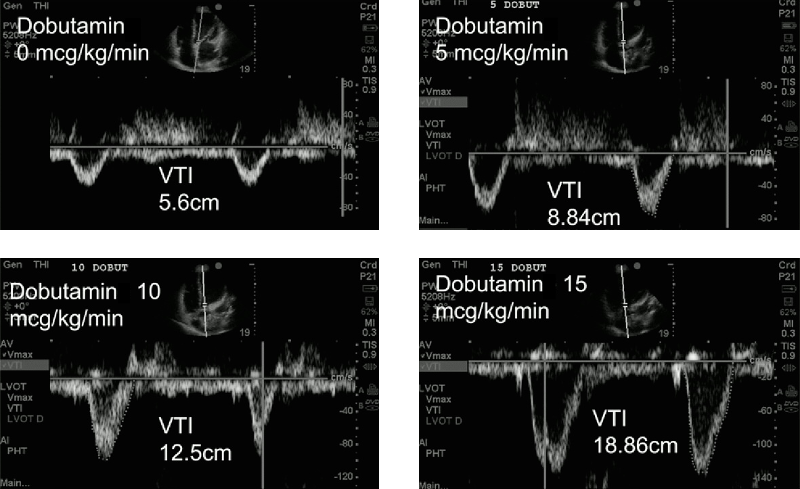

erweiterte Therapiesteuerung anhand der VTILVOT

• Inotropikasupport

• Gabe von Dobutamin, 3 min. später Kontrolle der VTI und ggf. weiterer Steigerung des Dobutamins

Therapiesteuerung_VTI

... wie geht es weiter?